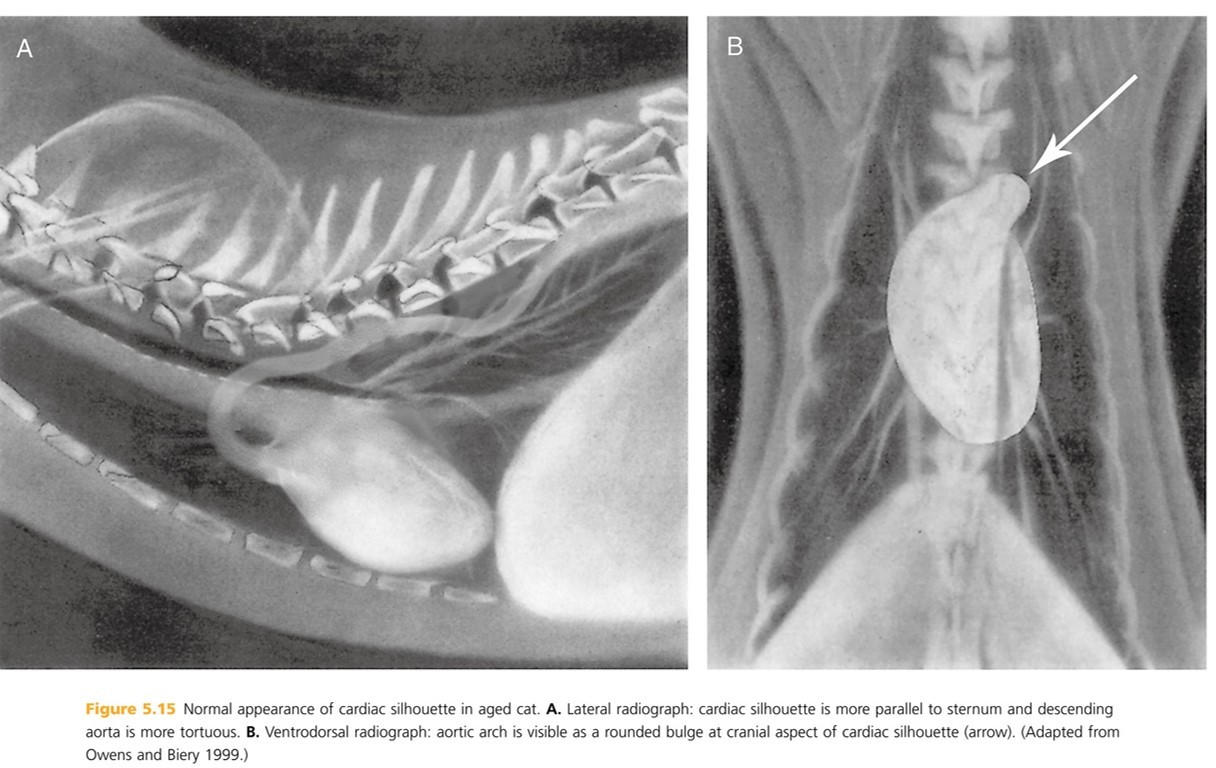

A cat cardiac silhouette radiograph is _____ at the crainal and caudal (compaired to a dog) and ends and appears to have a “_____” shape. The position of the apex is more _____ than a dogs, usually located on or left of midline but sometimes right of midline. In older cats, the cardiac silhouette is more ______ in position.

thinner

lemon

vairable

horizontal (more parallel with the sternum)

In cats, the width of the cardiac silhouette on a lateral radiograph is ___ intercoastal (b/t ribs) spaces. Width on lateral rad is ____ the width of the thoracic cavity.

2

1/2 - a dog is 2/3 the width of the thoracic cavity.

How does the caudal trachea differ in the cardiac silhouette of a cat vs. a dog?

Cat tracheas DO NOT bend ventrally at the heart base.

Dog traches DO curve slightly ventral tat the heart base